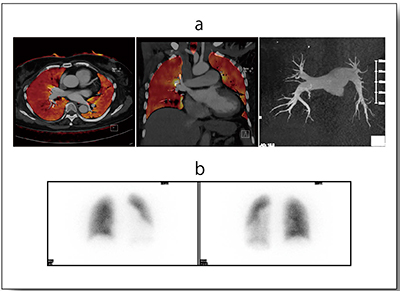

CTEPHの画像診断では上記のほかに,Dual Energy Imagingを用いた“Lung PBV”が有用である。Lung PBVは,Three-material decompositionにより肺野の造影剤成分を抽出し,ヨードマップを作成する。このヨードマップは,通常CT画像に重ね合わせて表示することが多い(図1)。

図1 CTEPHの肺血流シンチグラム(a)とLung PBV(b)

肺血流シンチグラム所見に似た楔形,区域性の灌流低下域が認められる。